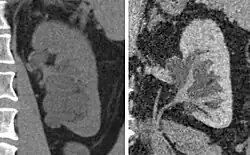

Non-contrast CT (at left) showing peripelvic fluid accumulations, which may be hydronephrosis. CT urography (at right) reveals non-dilated calyces and pelvises. The fluid accumulations are thus peripelvic cysts.

Parapelvic cysts originate from around the kidney at the adjacent renal parenchyma, and plunge into the renal sinus. Peripelvic cysts are contained entirely within the renal sinus, possibly related to dilated lymphatic channels. When viewed on CT in absence of contrast, they can mimic hydronephrosis.[15] If symptomatic, they can be laparoscopically decorticated - removal of the outer layer or cortex.[16]